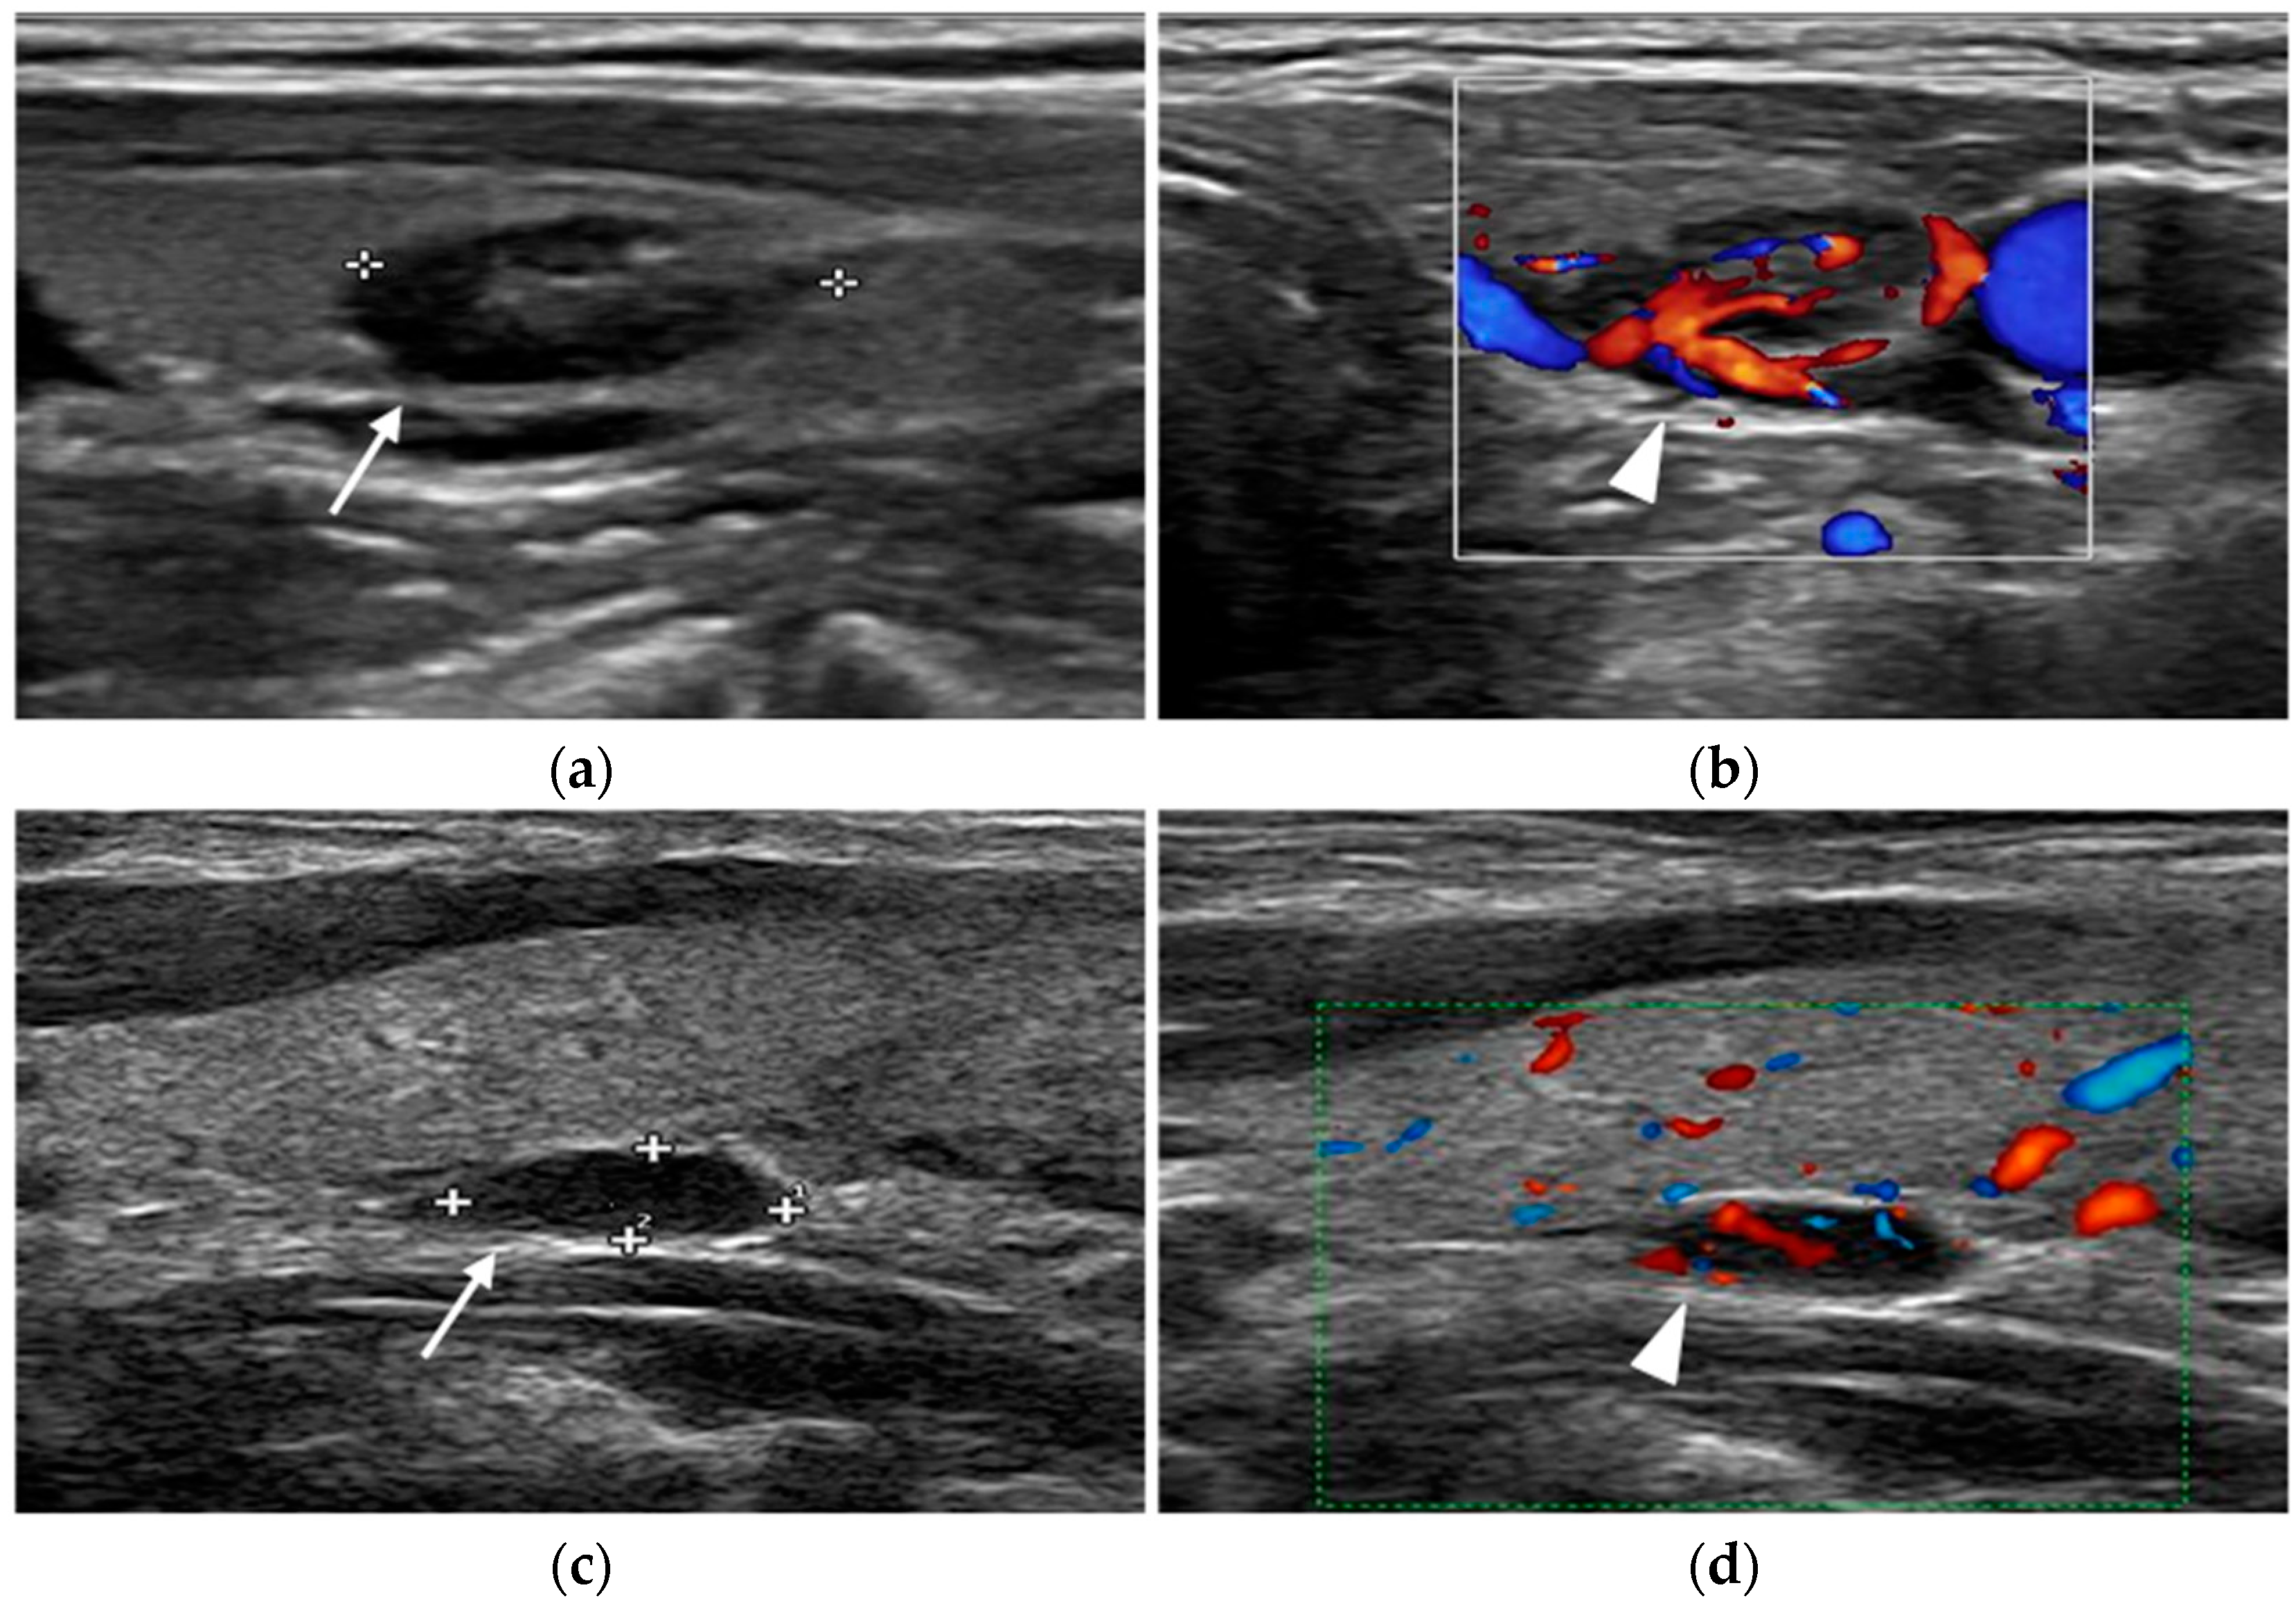

During an ultrasound examination, the patients lie supine with a pillow under their shoulders to extend the neck. Gray-scale imaging is performed using a high-frequency linear transducer. The examination encompasses the transverse plane from the carotid arteries to the midline and the craniocaudal plane from the hyoid bone or carotid bifurcation to the thoracic inlet. Parathyroid images are both obtained in transverse and longitudinal views. Color Doppler and power Doppler imaging techniques are used alongside gray-scale ultrasound to enhance the detection of prominent feeding arteries (Figure 2).

Figure 2.

Parathyroid adenomas. In two different patients, ultrasound shows a markedly hypoechoic nodule (arrow) close to the left lobe (a) and right (c) thyroid lobe. Color-doppler images highlight the feeding vessels (arrowhead) inside the lesions (b,d).